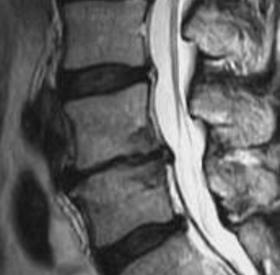

La lombalgia, denominata anche comunemente "dolore lombare" o "mal di schiena", rappresenta un quadro clinico caratterizzato da dolore localizzato nella parte bassa della colonna vertebrale (fig.1 – fig.2), propriamente detta colonna lombare o lombo-sacrale. Può essere causata…

La stenosi lombare è un'abnorme ristrettezza del canale vertebrale osteolegamentoso e/o dei forami intervertebrali (fig.1), ed è causa di una compressione del sacco tecale e/o delle radici spinali caudali (fig.2). Il restringimento può essere mono o plurisegmentario. Le…